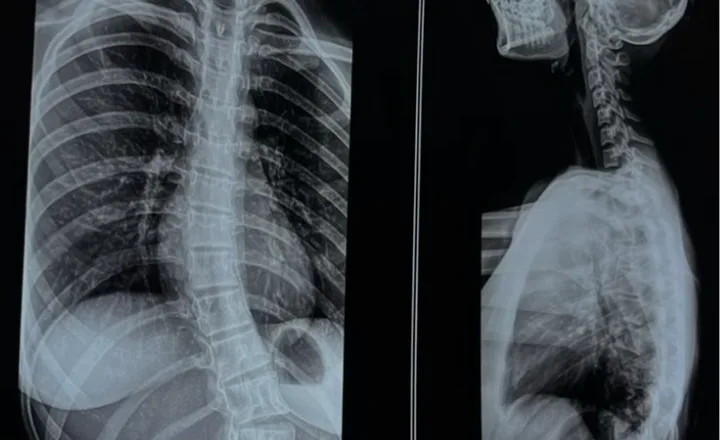

Spinal cord injury (SCI) is a neurological condition that occurs when damage to the spinal cord influences communication between the brain and different parts of the body. The functional impact varies depending on the injury level, severity, and individual health factors, often affecting mobility, sensation, or coordination. Long-term management commonly includes structured rehabilitation programs, physiotherapy, and assistive support strategies.

A spinal cord injury can result from trauma, compression, or medical conditions affecting spinal tissues. Depending on the injury location, individuals may experience variations in movement, muscle strength, sensory perception, or autonomic function. Because every injury profile is unique, multidisciplinary care involving neurologists, rehabilitation specialists, and physiotherapists is typically recommended to support long-term functional goals.